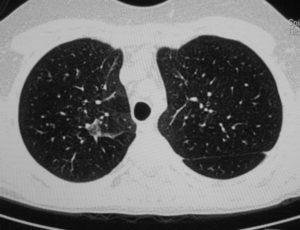

Расшифровка снимков происходит в тот же день. Полученные изображения анализирует врач-рентгенолог, который и выдает заключение. Определить верный диагноз непросто, ведь среди нескольких десятков оттенков черного, серого и белого необходимо вычленить несоответствующий норме и интерпретировать результат. Представим Вашему вниманию несколько фото томографии грудной клетки:

КТ без контраста у пациента с интерстициальным заболеванием легких в анамнезе и трансплантацией правого легкого показывает суженный участок анастомоза правого бронха (красная стрелка). Собственное левое легкое уменьшено в размерах, с признаками бронхоэктазов, бронхиолоэктазов (черная стрелка). Сужение центрального дыхательного пути на выдохе у трансплантированного легкого (синяя стрелка).

Выпот (красные стрелки) в обеих плевральных полостях.